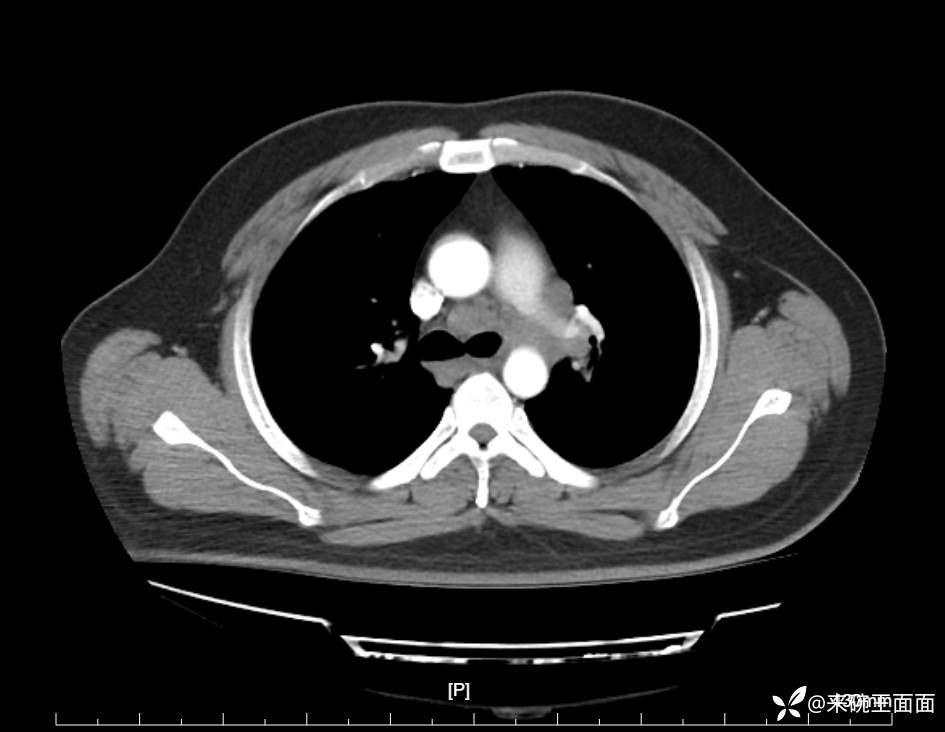

性别:男

年龄:27岁

主诉:胸闷胸痛数月余,休息后可自行缓解,无咯血症状。

个人史:数年吸烟史,具体不详。